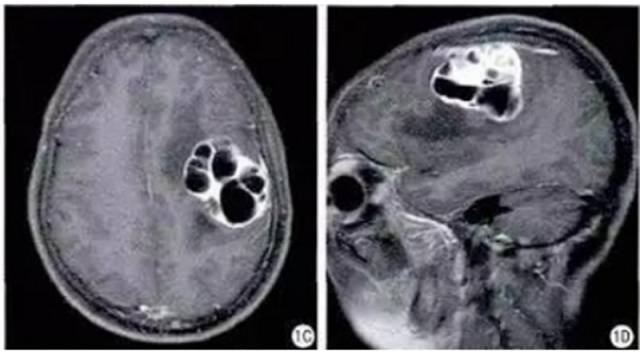

病理结果:血管瘤型脑膜瘤

CT平扫(骨窗 脑窗)